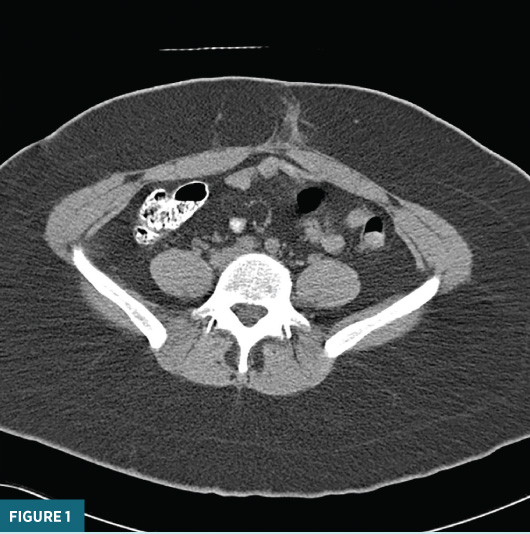

An unenhanced axial CT image inferior to the umbilicus  (Figure 1) demonstrated ill-defined soft tissue inflammatory changes within the  anterior abdominal subcutaneous fat.